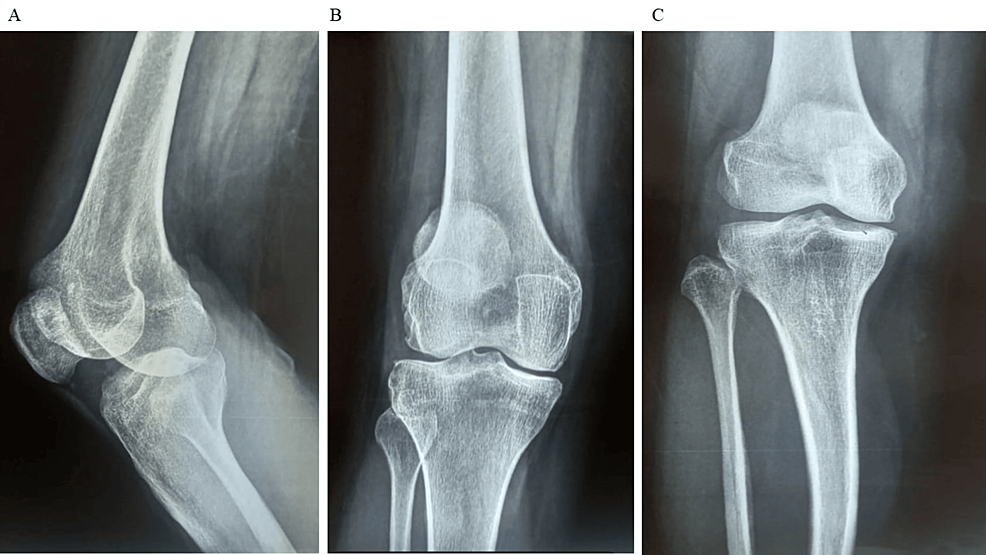

除了骨關(guān)節(jié)炎外,15名參與者還被發(fā)現(xiàn)患有骨缺損,占該隊(duì)列的30%。這些缺損包括各種情況,例如骨折、退行性骨病或先天性畸形,突顯了研究中涉及的骨科問題多種多樣。下圖1顯示了開始干細(xì)胞治療之前的骨骼側(cè)視圖和前后視圖。

圖1:顯示了開始干細(xì)胞治療之前的骨骼側(cè)視圖和前后視圖。

圖1:A:干細(xì)胞治療前(側(cè)視圖),B:干細(xì)胞治療前前后位(AP)視圖,C:干細(xì)胞治療前前后位(AP)視圖。